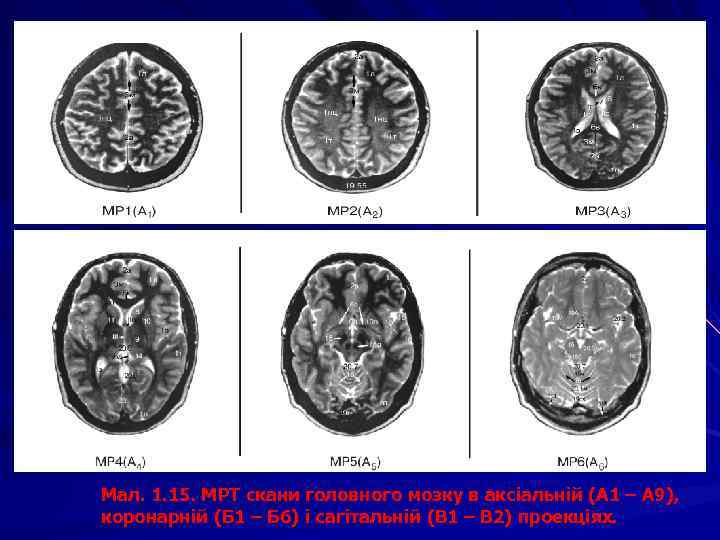

Мал. 1. 15. МРТ скани головного мозку в аксіальній (А 1 – А 9), коронарній (Б 1 – Б 6) і сагітальній (В 1 – В 2) проекціях.

Мал. 1. 15. МРТ скани головного мозку в аксіальній (А 1 – А 9), коронарній (Б 1 – Б 6) і сагітальній (В 1 – В 2) проекціях. 1 – частки великого мозку: 1 л – лобова, 1 т – тім’яна, 1 с – скронева, 1 п – потилична, 1 о – острівцева, 1 нц – напівовальний центр. 2 - щілини великого мозку: 2 а – поздовжня, 2 б – поперечна. 3 т – потилично-скронева, 3 у – каудально -таламічна, 3 ф - 3 – борозни: 3 а – центральна, 3 б – бічна, 3 в – передцентральна, 3 г – верхня лобова, 3 д – нижня лобова, 3 е – зацентральна, 3є – нюхова, 3 ж –потиличні, 3 и – шпорна, 3 з – півмісяцева, 3і – верхня скронева, 3ї – нижня скронева, 3 к – острівцеві, 3 л – мозолистого тіла, 3 м – поясна, 3 н – підтім’яна, 3 н – нижня тім’яна, 3 о – тім’яно-потилична, 3 п – каудально-таламічна, 3 р – гіпокамп 3* звивини: 3 а* – передцентральна, 3 б* – зацентральна, 3 в* – верхня лобова; 3 г* – середня лобова, 3 д* – нижня лобова, 3 ж*– верхня скронева, 3і* – середня скронева; 3 и* – нижня скронева; 3 к* – верхня тім’яна часточка, 3 л* – нижня тім’яна часточка; 4 – шлуночки мозку: I, ІІ – бічні шлуночки: п – передній, з – задній, н – нижній роги, с – судинне сплетіння, т – тіло; III шлуночок: з – зорова, л – лійкова заглибини; с – міжталамічна спайка, о – міжшлуночкові отвори; IV шлуночок: б – бічний, с – серединний отвори. 5 – водопровід мозку. 6 – мозолисте тіло: 6 в – валок, 6 с – стовбур, 6 к – коліно, 6 д – дзьоб, 6 п – променистість; 6* – передня комісура (спайка). 7 – прозора перегородка: 7 п – порожнина прозорої перегородки. 8 – хвостате ядро. 9 – таламус, 9* – гіпоталамус. 10 – смугасте тіло. 11 – внутрішня капсула: 11 п – передня ніжка, 11 з – задня ніжка, 11 к – коліно. 12 – гіпофіз. 13 – зорове перехрестя. 14 – шишкоподібне тіло. 15 – ніжка мозку, 15 а – червоне ядро, 15 б – горбки чотиригорбистості. 16 – мозочок: 16 ч – черв ’як, 16 м – мигдалик, 16 я – ядра. 17 – довгастий мозок, 17 ц – центральний канал. 18 – міст. 19 – кровоносні судини, 19 А – мозкові артерії: 19 а – передня, 19 m – середня, 19 p – задня; 19 v – вертебральна, 19 k – сонна, 19 c – мозочкова; 19 V – мозкові вени: 19 iv – внутрішня вена мозку; 19 vj – велика вена (Галена); 19 S – синуси: 19 r – прямий, 19 ks – стік синусів, 19 ss – сагітальний синус. 20 – цистерн підпавутинного простору: 20. 1 – мозочково-довгаста (бульбарна); 20. 1 а – валекула; 20. 1 м – верхня мозочкова; 20. 2 – бічної ямки великого мозку; 20. 3 – міжніжкова; 20. 4 – зорового перехрестя; 20. 5 – навколомозолиста; 20. 6 – великої вени (чотиригорбистості); 20. 7 – оточуюча; 20. 8 – мосто-мозочкова; 20. 9 – цистерни моста; 20. 10 – конвекситальний субарахноїдальний простір. Присінковозавитковий нерв – позначено*, мозочковий серп – стрілкою, мозочковий намет – подвійною стрілкою. 21 – кістки черепа: 21 р – решітчаста, 21 л – лобова, 21 к – клиноподібна, 21 тс – турецьке сідло, 21 т – тім’яна, 21 п – потилична, 21 с – скронева, 21 сх – схил. 22 – ламбдоподібний шов. 23 – великий потиличний отвір. 24 - орбіта.